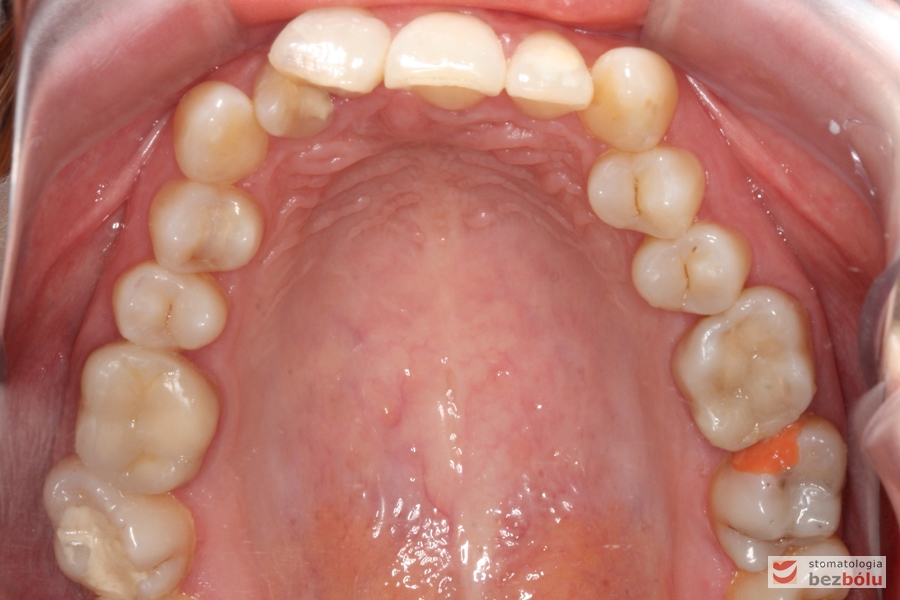

Pacjentka lat 26 zgłosiła się do gabinetu celem korekcji uśmiechu. Głównym zmartwieniem były problemy estetyczne, które znacznie wpływały na jakość życia pacjentki. Wykonano leczenie zachowawcze zębów oraz analizę cefalometryczną i analizę modeli diagnostycznych. Zaplanowano leczenie aktywne aparatem DAMON dla szczęki i żuchwy, które trwało 2 lata. Po fazie leczenia aktywnego rozpoczęto leczenie retencyjne z użyciem szyny tłoczonej dla szczęki i retainera stałego dla żuchwy.